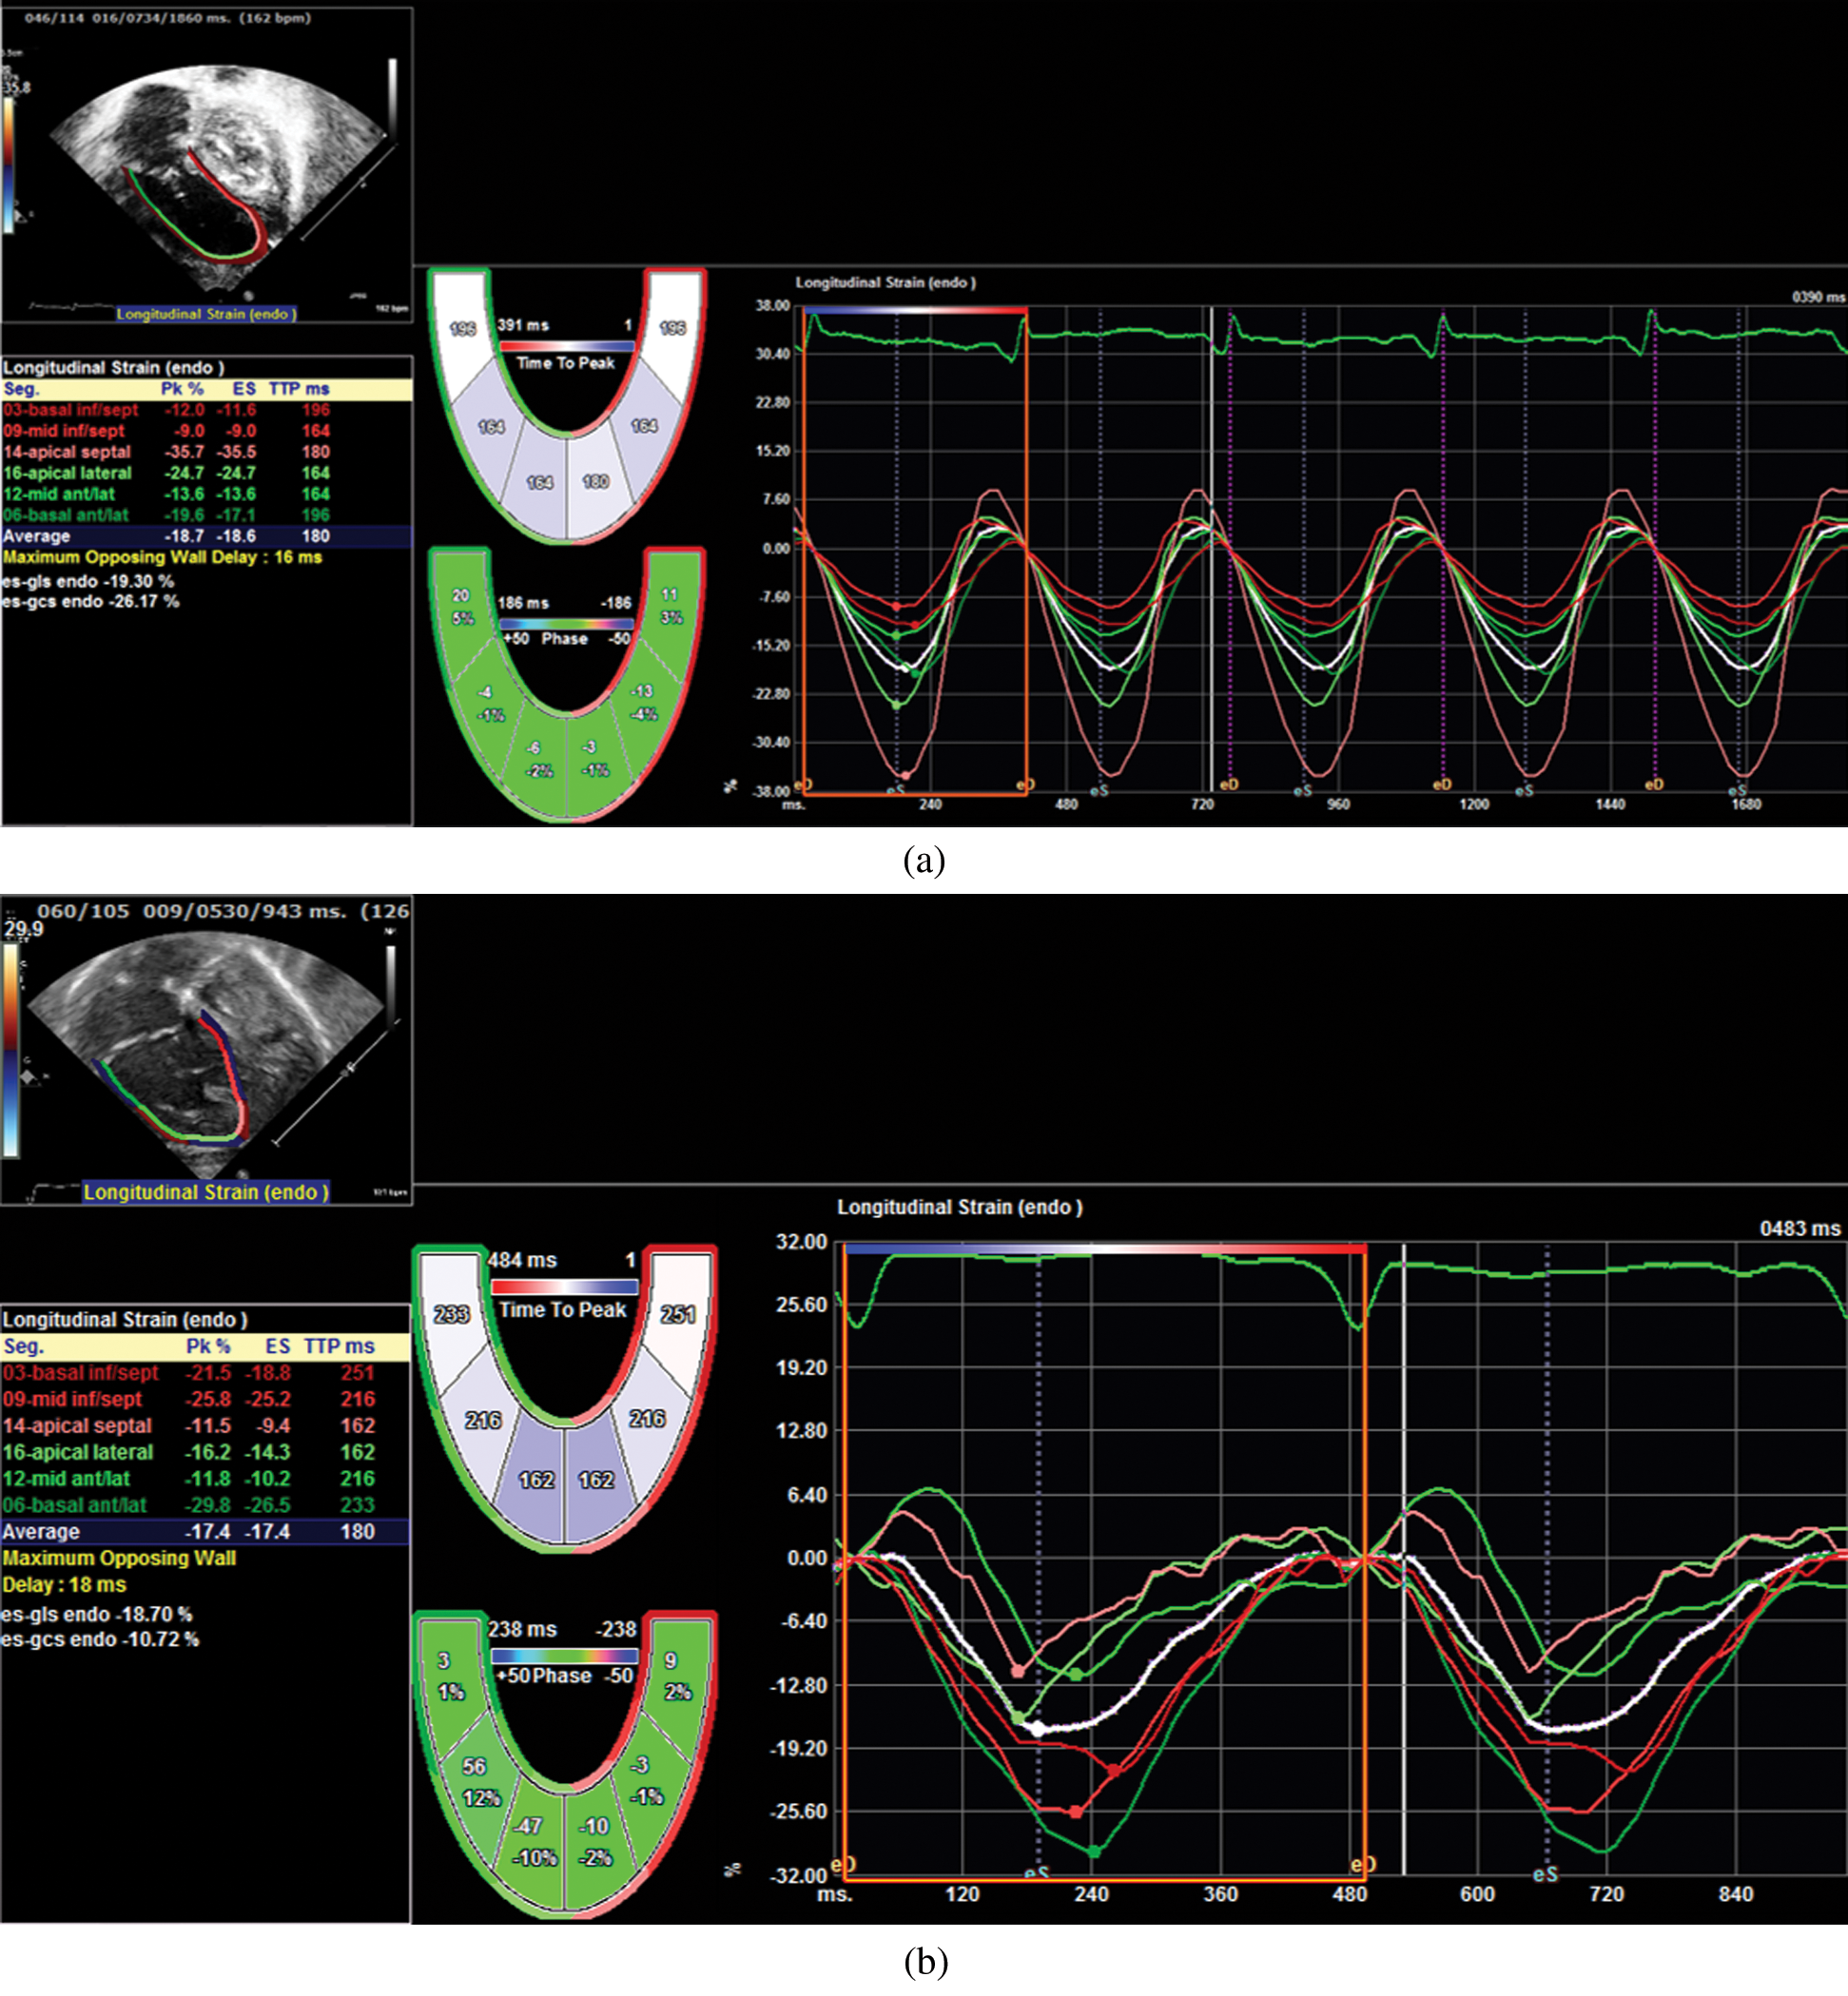

There were no differences in TAPSE, FAC, and LS between the RVPAS group and the mBTS group in all the echocardiographic time points (Fig. 2). At 90-days and 200-days post-Norwood assessment, the mBTS group showed a significant improvement in LS compared to pre-Norwood assessment (∆LS). This finding, albeit present, was no statistically significant at 30-days and 140-days post-Norwood assessment. At 200-days post Norwood evaluation mBTS group showed a significantly smaller RV compared to RVPAS group.

Figure 2: LS measurement at 90-days post Norwood evaluation. Image a shows LS in a patient treated with BTS. Image b shows LS in a patient treated with RVPAS